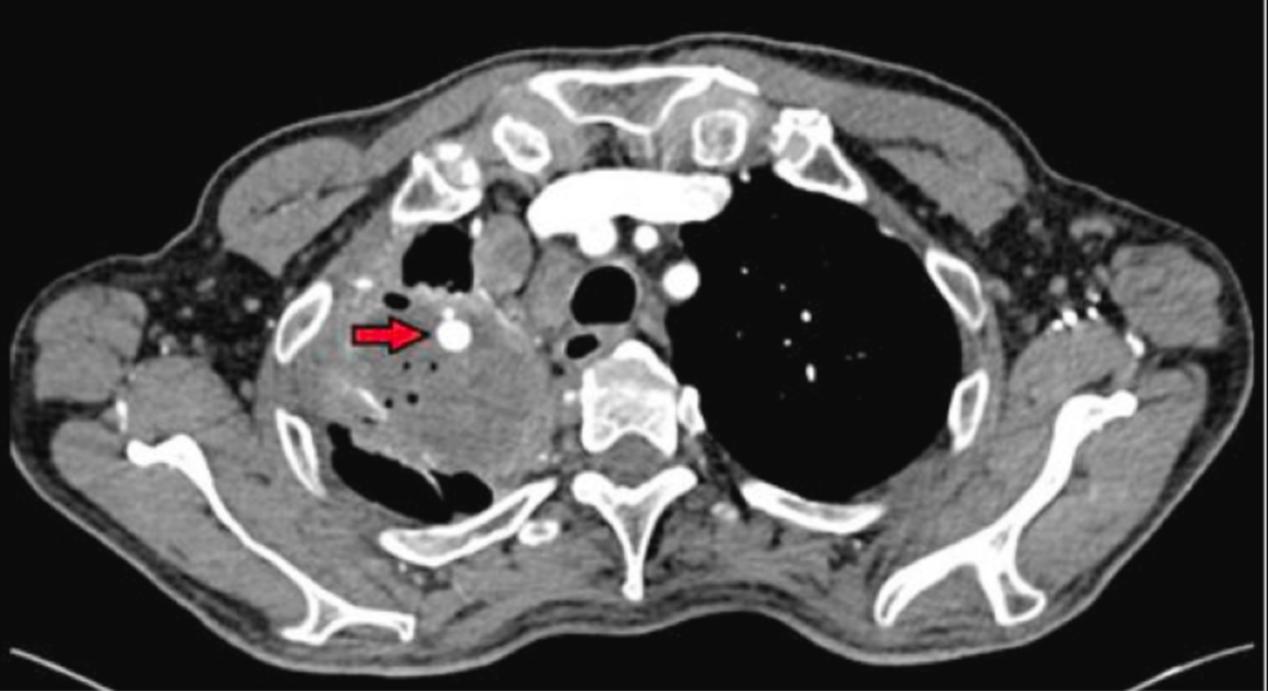

第3天,胸部CT扫描显示广泛的右上叶囊性和实变性改变,伴有多个纵隔淋巴结肿大(图1)。第7天患者接受了支气管肺泡灌洗(BAL),但没有显示出细菌感染或恶性肿瘤的证据。革兰染色、培养和结核病检查均为阴性。BAL液主要为中性粒细胞(96%为中性粒细胞),并生长根霉。临床中细菌性肺炎的诊断基于疾病的严重性和以中性粒细胞为主的BAL液。患者体温峰值稳定,临床反应良好,口服奥格汀2周后出院。安排肺科门诊随访6周。

图1

CT扫描还显示腔内有一个8×7mm大小的动脉瘤,似乎起源于右上叶肺动脉的一个亚段分支(图2)。

图2